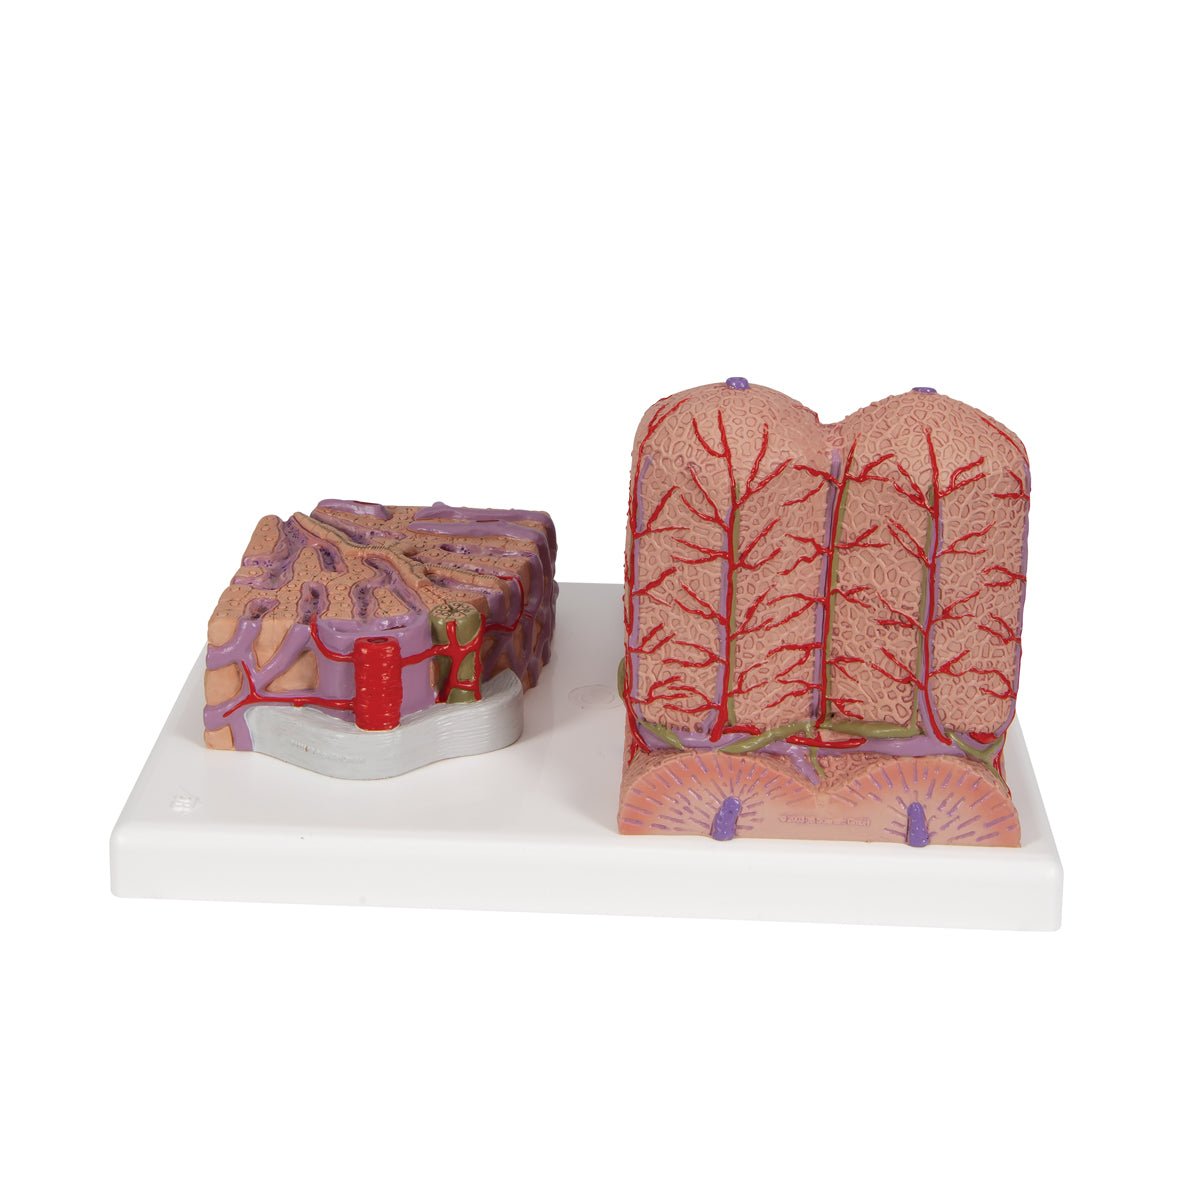

Salg af anatomiske modeller er det bærende element i eAnatomi, selvom vi også bruger mange ressourcer på at udvikle vores egne anatomiske materialer som fx plakater. Anatomiske modeller anvendes til forskellige formål og kan både vise afgrænset væv, organer samt organsystemer. Søger du en simpel model af knoglevæv eller måske en avanceret torso-model baseret på MRI teknologi, kan du finde det hele på eanatomi.com.